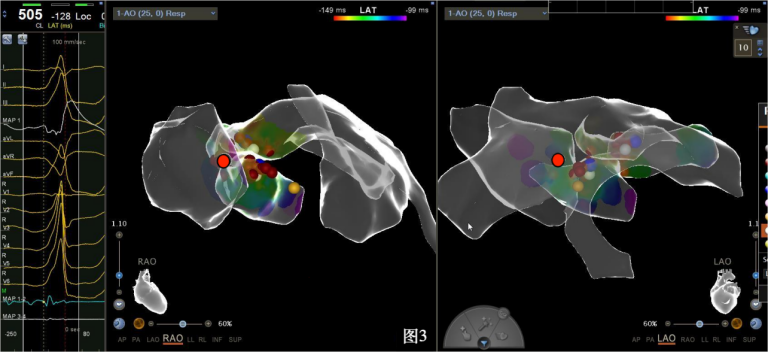

手术中,周明礼团队凭借其丰富的临床经验和精湛的技术,穿刺右股动脉后,将消融大头顺利送入主动脉,于主动脉瓣上标测到最早点(图3红色点)领先体表8ms,电位不理想,果断去到主动脉瓣下左室穹顶部标测,标测到最早点(图4白色点)领先体表25ms,放电消融3s,早搏消失,消融90s后观察2min后,早搏恢复,在该有效点周边补充消融,早搏依旧未能消失,考虑起源点较深,内膜消融未能透壁损伤到起源,随